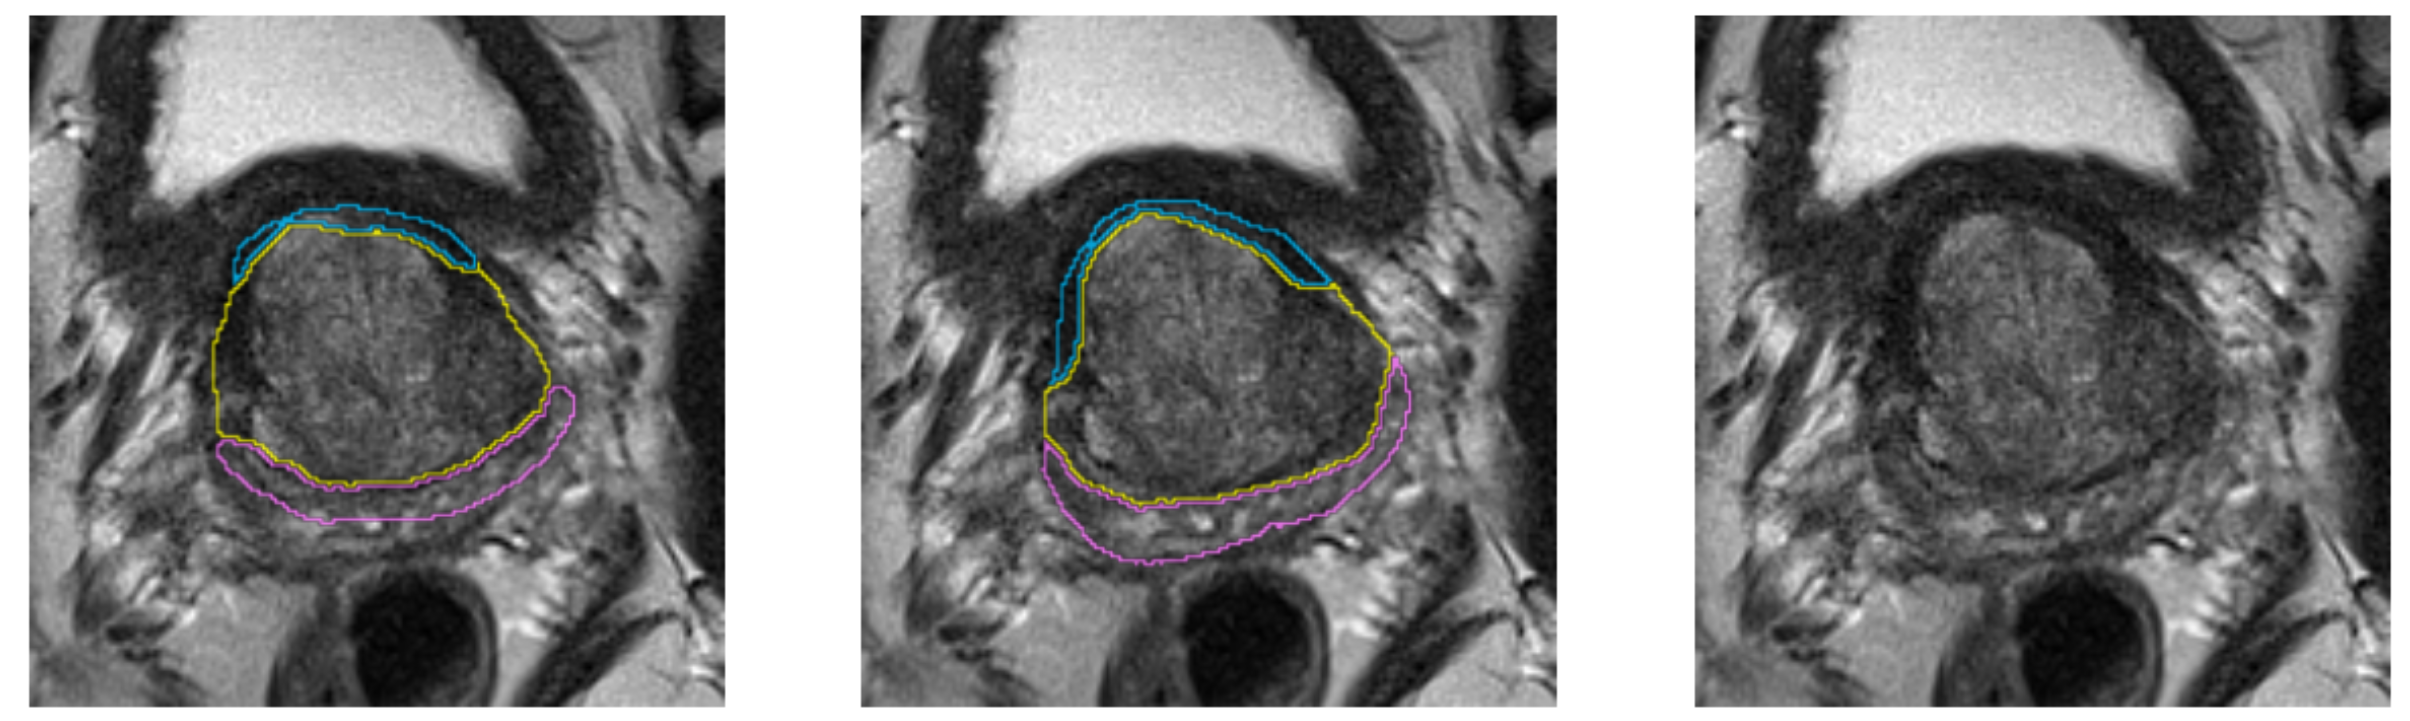

Segmentation Example. Left: automatic, center: manual segmentation